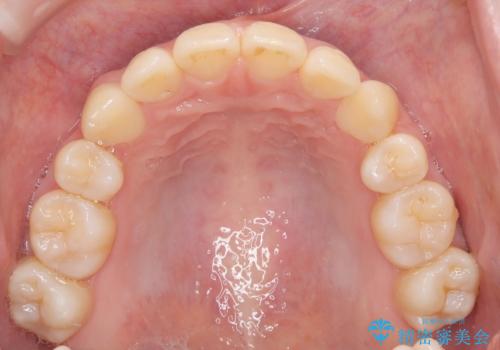

- 八重歯が気になるとのことでご相談いただきました。診察すると、歯列のスペース不足により犬歯が外側に飛び出している状態でした。このままでは歯を並べるスペースが足りないため、抜歯矯正が必要と判断。治療は目立ちにくいインビザラインで行い、歯の移動をサポートするためにゴムかけ(顎間ゴム)を併用する計画を立てました。

抜歯後、インビザラインを用いて少しずつ歯を移動させ、空いたスペースに八重歯を整列させました。さらに、ゴムかけを行うことで上下の噛み合わせを適切に調整。治療後は、八重歯が綺麗に並び、バランスの取れた歯並びと自然な噛み合わせを実現できました。患者様にも「仕上がりがとても綺麗で、口元の印象が変わった」とご満足いただきました。